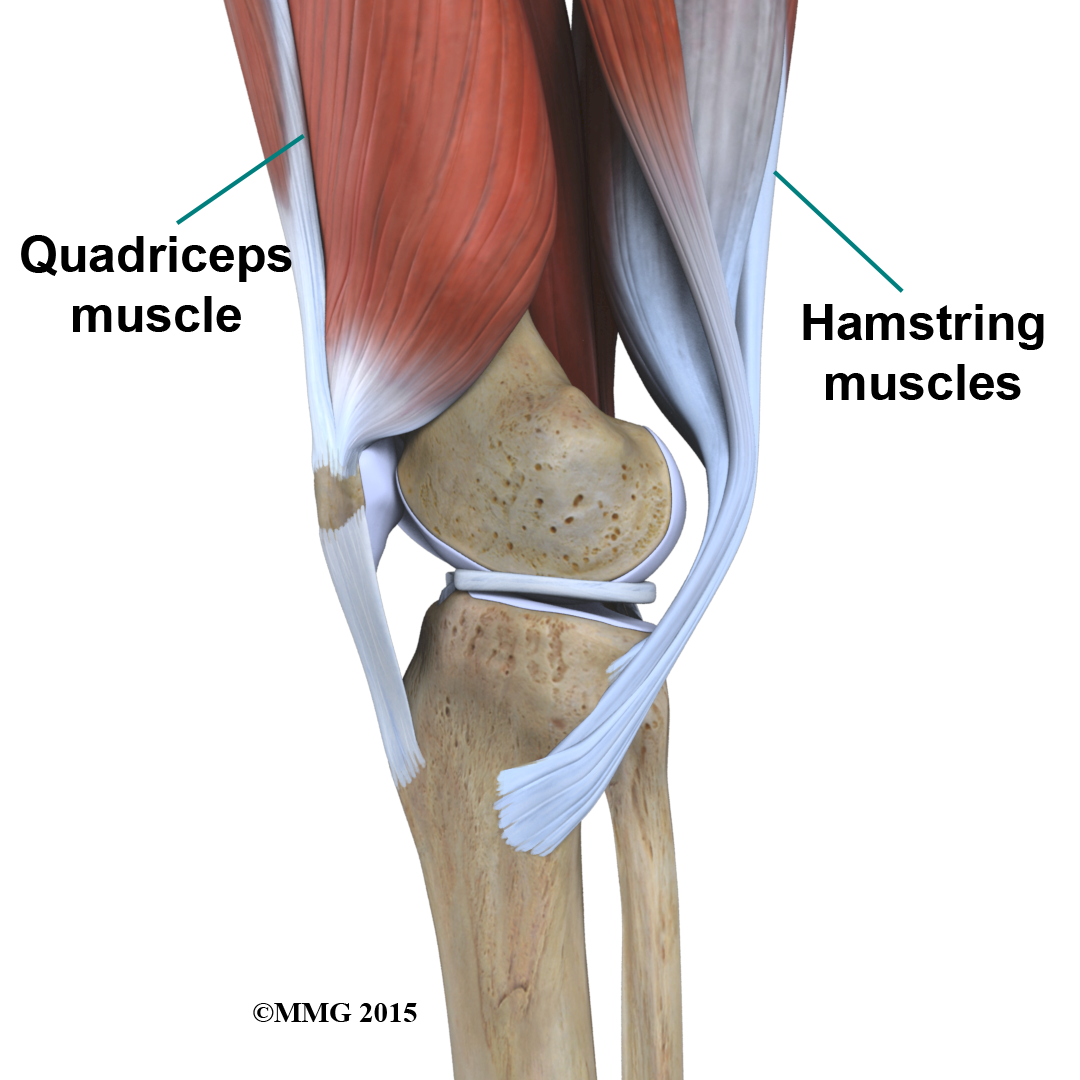

There it is called the quadriceps tendon since it attaches to the quadriceps muscles in the front of the thigh. The hamstring muscles on the back of the leg also have tendons that attach in different places around the knee joint. These tendons are sometimes used as tendon grafts to replace torn ligaments in the knee.

Muscles

The extensor mechanism is the motor that drives the knee joint and allows us to walk. It sits in front of the knee joint and is made up of the patella, the patellar tendon, the quadriceps tendon, and the quadriceps muscles. The four quadriceps muscles in front of the thigh are the muscles that attach to the quadriceps tendon. When these muscles contract, they straighten the knee joint, such as when you get up from a squatting position.

The way in which the kneecap fits into the patellofemoral groove on the front of the femur and slides as the knee bends can affect the overall function of the knee. The patella works like a fulcrum, increasing the force exerted by the quadriceps muscles as the knee straightens. When the quadriceps muscles contract, the knee straightens.

The way in which the kneecap fits into the patellofemoral groove on the front of the femur and slides as the knee bends can affect the overall function of the knee. The patella works like a fulcrum, increasing the force exerted by the quadriceps muscles as the knee straightens. When the quadriceps muscles contract, the knee straightens.

The are the muscles in the back of the knee and thigh. When these muscles contract, the knee bends.